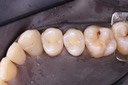

Photos of Clinical Operations

Drs. Peter Kearney, Terry McKay, John St. Germain, and Laurie Vanzella - Mentors